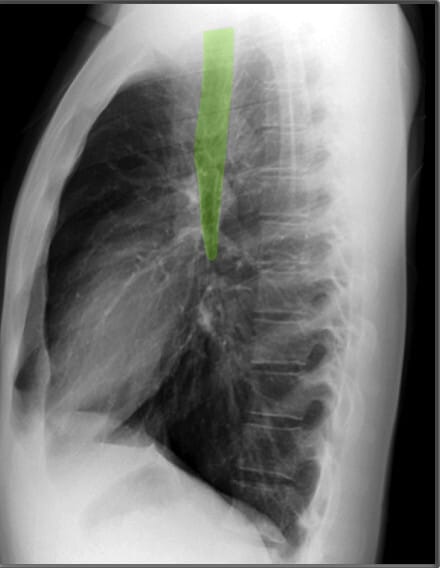

Lateral View of Chest X-ray

측면 영상은 폐, 심장 및 척추의 깊이를 평가하는 데 유용합니다.

하늘색이 Vertebral bodies, 파란색 (코발트 블루)가 Pedicles| 기관 (Trachea) |

| ✅ 흉부 중앙에서 공기가 가득 찬 검은 색의 관 형태로 보이며, 정상적으로는 앞쪽으로 약간 기울어져 있습니다. 협착되거나 편위된 경우 기도 병변을 의심할 수 있습니다. |